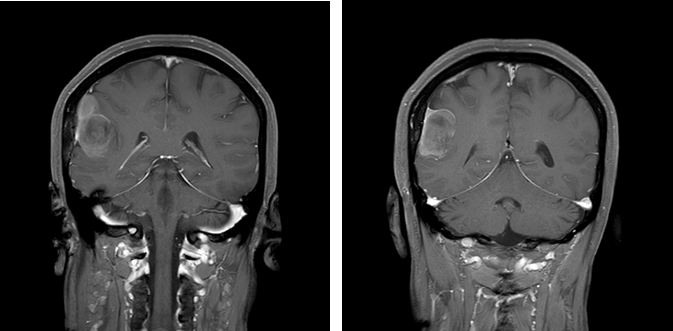

CASE 2

男,34 岁

右侧顶部大脑镰旁占位,信号均匀,增强可见明显强化,边界清晰,见脑膜尾征。

诊断:右侧顶部脑膜瘤